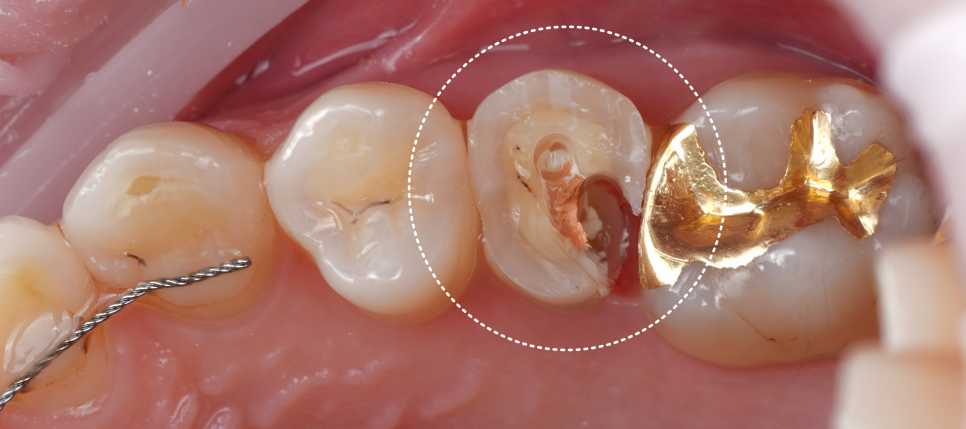

촬영일 : 251124

기존에 남아 있던 충전물·임시재를 깨끗이 제거해서 충치와 재료 경계를 깔끔하게 정리했고 안쪽 바닥은 보험이 되는 재료(GI)로 두 면을 먼저 채워 뼈대(바탕)를 만들어 주기로 했죠.

이후 그 위에 신경치료를 위해 만든 구멍을 메우는 작업(코어, Core)와 함께 씹는 면 전체를 포괄적으로 덮는 레진 빌드업으로 형태(교두와 벽)를 다시 만들어 드렸어요.

쉽게 말하면 안쪽은 단단하게 기초를 다지고 바깥은 레진으로 치아 본래 모양과 기능을 다시 만들어 드린 것이라고 생각하시면 됩니다.